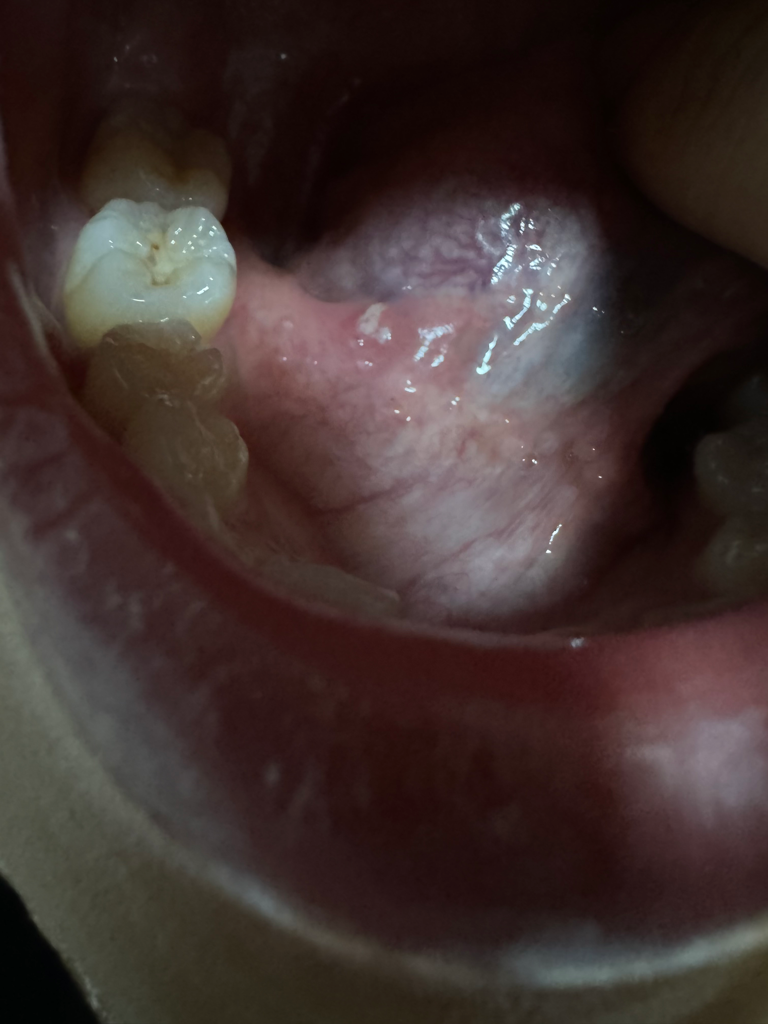

혀 밑에 통증이 자꾸 느껴져서 봤더니 흰색 염증이 있어요.

사진보시면 흰색 염증같은 거 있는 곳에 통증이 있어요.

동그라미 쳐놓은거는 알보칠바르기전이고 동그라미 없는거는 알보칠을 바른 후 입니다

• 2번 째 사진